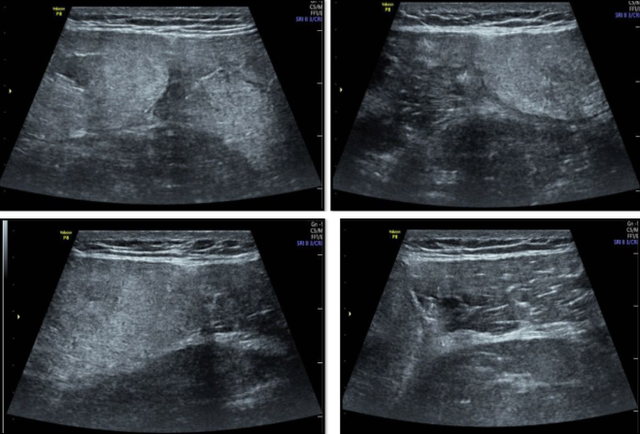

Kết quả siêu âm cho thấy hình ảnh vùng giảm âm trong tổ chức cơ tứ đầu đùi phải và trái

Siêu âm cho thấy hình ảnh vùng giảm âm trong tổ chức cơ tứ đầu đùi phải, trái, theo dõi tổn thương cấp.